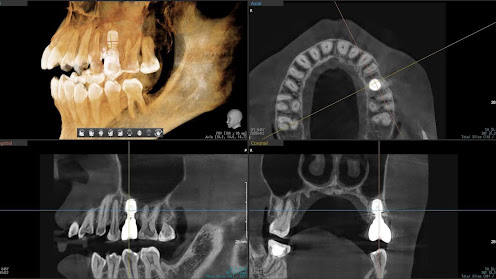

Before

枚方市のインプラントの症例

After

M・I 様 女性 70代

症状としては、左下56は、歯周病で欠損したと考えられるが、かなりの骨欠損をともなっていた。左上456に関しては、動揺が大きく、炎症が起き、排膿、および、歯性上顎洞炎を起こしていた。

治療法としては、動揺がひどくなってきて、炎症の症状もあったため、左上56の抜歯を希望。インプラント治療をその後、希望したため、左上4に関しては抜歯即時埋入。左上6に関しては、既存骨1から2mmでインプラント治療が厳しい状態であったが、グラフトレスサイナスリフトを行い、治療期間5か月はかかるということを説明して、インプラント埋入をおこないました。その後、2か月半後、大幅に骨が欠損している下顎56に対して、ショートインプラントを使用して、下顎神経の損傷を避けて、インプラント埋入を終えています。その後2か月後に光学印象で印象を行い、上顎刺億456歯、3ユニットのジルコニアブリッジを装着。下顎左側56に関しては、骨欠損が大きいため、歯冠長がだいぶ長くなるため、ジルコニアの連結冠を装着して治療を終えた。

治療結果は、上顎6に関しては、既存骨が少なく、厳しい治療ではありましたが、5か月で治療を終え、患者様の負担を最小限に抑えるができたと考えます。(従来のサイナスリフトでは、このようなケースでは1年以上、1年程度の治療期間がかかるか、治療が不可能と言われるケースだと考えます。)また、下顎は骨欠損が大きく、下歯槽管のリスクが起きることが考えられますが、ショートインプラントを使用することで安全に治療を行うことができました。

治療の期間・回数:治療期間5か月(上顎456 3ピースブリッジの治療は5か月(上顎既存骨が2mm程度しかなく、骨結合に時間がかかるケースであったために、5か月の治療期間が必要であった。)(左下56に関しては2か月半で治療を終えています。)治療回数は、13回。

治療の価格:1,474,000円(税込)

治療費の内訳:左上46および左下56のインプラント基本料(フィックスチャー及び手術費用、投薬費用、レントゲン費用、インプラント上部費用(アバットメントおよびジルコニアクラウンの費用用)330000円(税込み)×4本分 1320000円(税込)。左上5ジルコニアポンテック費用88000円(税込)。オプション費用、左上4抜歯即時埋入加算(人工骨費用を含む)+グラフトレスサイナスリフト費用 33000円(税込)、左上6グラフトレスサイナスリフト費用 33000円(税込)

治療のリスクや副作用:手術後に、痛みや腫れ、出血、合併症などを引き起こす可能性があります。噛む感覚がご自身の歯と異なる場合があります。見た目がご自身の歯と異なる場合があります。手術後にメインテナンスを継続しないと、インプラントが抜け落ちる可能性があります。